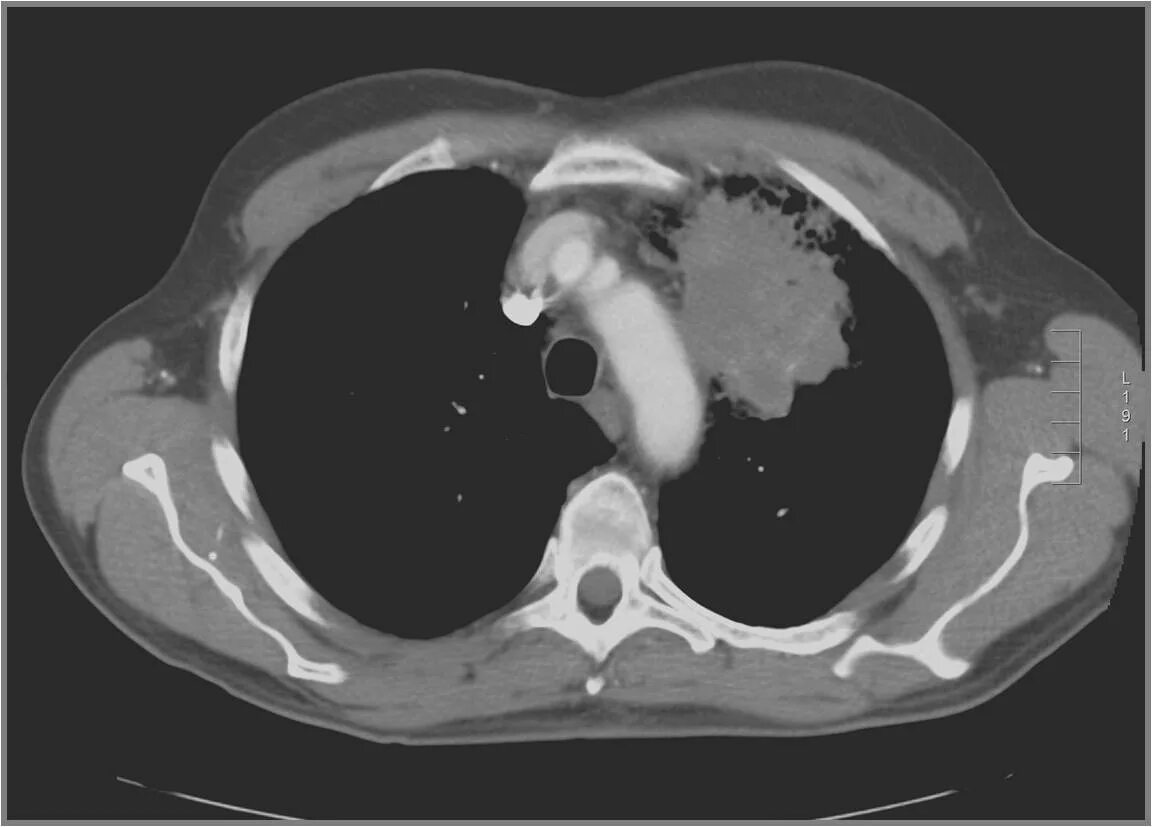

Как на кт выглядит рак